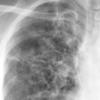

COPD

Date: 06/06/2004

Views: 14534